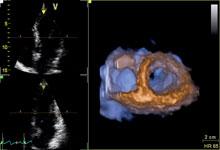

Cardiovascular Ultrasound | July 20, 2022

Enhanced features on the Philips EPIQ CVx ultrasound system provide a next level photorealistic 3D rendering, making it easy for users to interpret what they are seeing. The TrueVue feature enhances the sense of depth and space, producing images that appear natural and realistic to the human eye.

Watch the video to check out how TrueVue can help improve views of LAA and MV morphology.